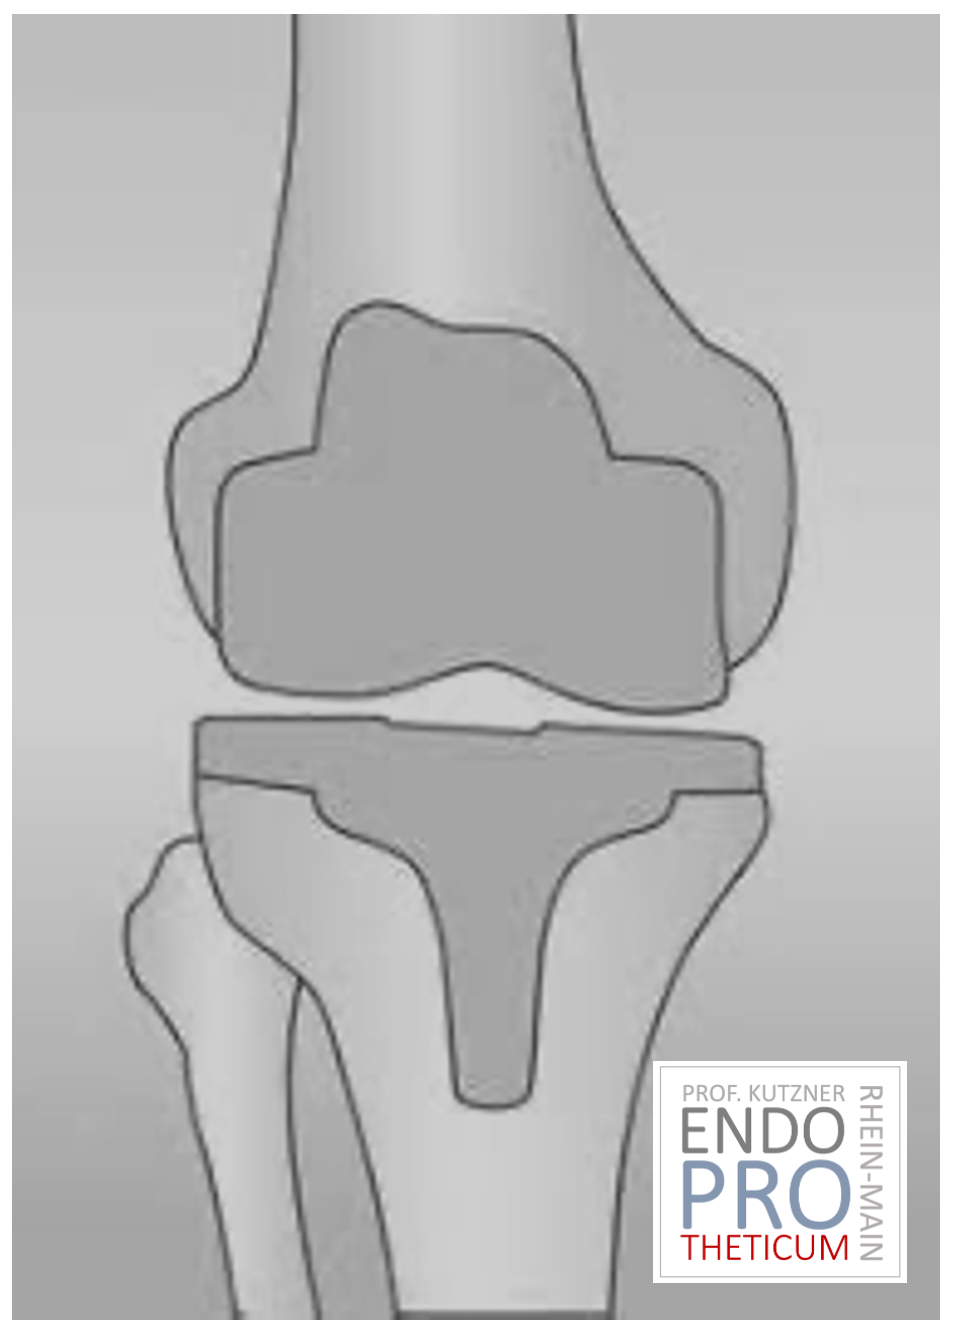

يحل مفصل الركبة الاصطناعي محل سطح الغضروف الذي دمره التهاب المفاصل العظمي. يظل العظم الأساسي في عظم الفخذ والرأس الظنبوبي سليمًا. يقارن البعض مفصل الركبة الاصطناعي الحديث بتتويج الأسنان؛ والمصطلح الدقيق هو ما يسمى بإعادة تسطيح اللقمتين. بين الأسطح الجديدة في الجزء العلوي والسفلي من الساق يوجد ما يسمى بالبطانة المصنوعة من البلاستيك الأبيض المقوى خصيصًا، والتي يمكن رؤيتها في صورة الأشعة السينية على أنها المسافة بين الأجزاء المعدنية.